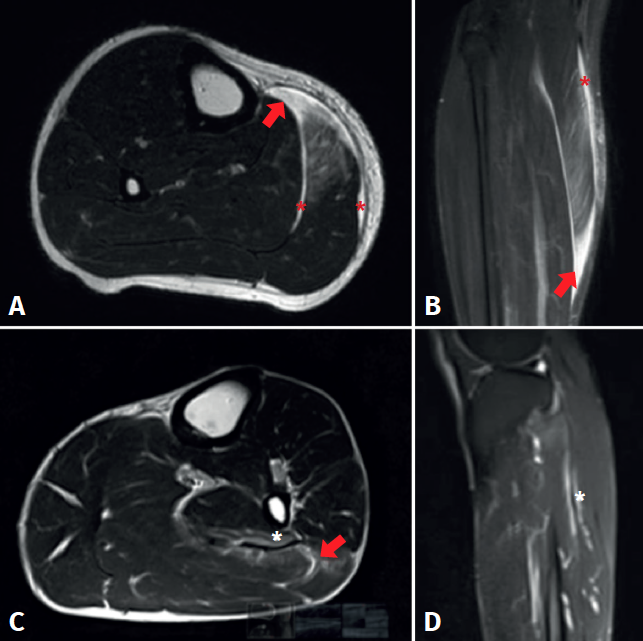

Figure 3. Magnetic resonance imaging study of triceps surae injuries. A: T2 axial sequence; B: coronal STIR sequence showing a fibrillar defect (red arrow) in the myotendinous junction of the medial gastrocnemius muscle, associated to a haematic collection in the peri-aponeurotic plane (red asterisks); C: T2 axial sequence; D: T2 FS sequence showing a fibrillar defect of the soleus muscle in the lateral proximal myotendinous junction (red arrow) associated to oedema of the adjacent muscle fibres (white asterisks).

Magnetic resonance imaging (MRI) facilitates the differential diagnosis, due to the greater anatomical details it provides. The signs that can be identified by MRI include oedema, muscle fibre rupture or discontinuities, muscle retraction and the presence of haematomas, as seen in Figure 3. With the use of MRI, muscle lesions are easily identified and located - the percentage frequency of damage to the medial gastrocnemius and the soleus being similar(33). In contrast, ultrasound is less capable in diagnosing these muscle injuries(9). In this context, 5 important soleus muscle injury sites have been described: at the medial proximal myotendinous junction (25.5%), the lateral proximal region (12.7%), the central and distal portion of the Achilles tendon (18.2%), and in the anterior and posterior myofascial plane (43.6%)(34), as can be seen in Figure 3. Balius et al. compared the capacity of ultrasound to diagnose soleus injuries versus MRI. The authors found that ultrasound was only able to detect 27.2% of the cases - the best detection performance corresponding to lesions in the posterior myofascial plane(34). Therefore, in cases with a strong clinical suspicion of tearing of the soleus muscle, and in the presence of normal ultrasound findings, MRI should be used in the differential diagnosis of the disorder.